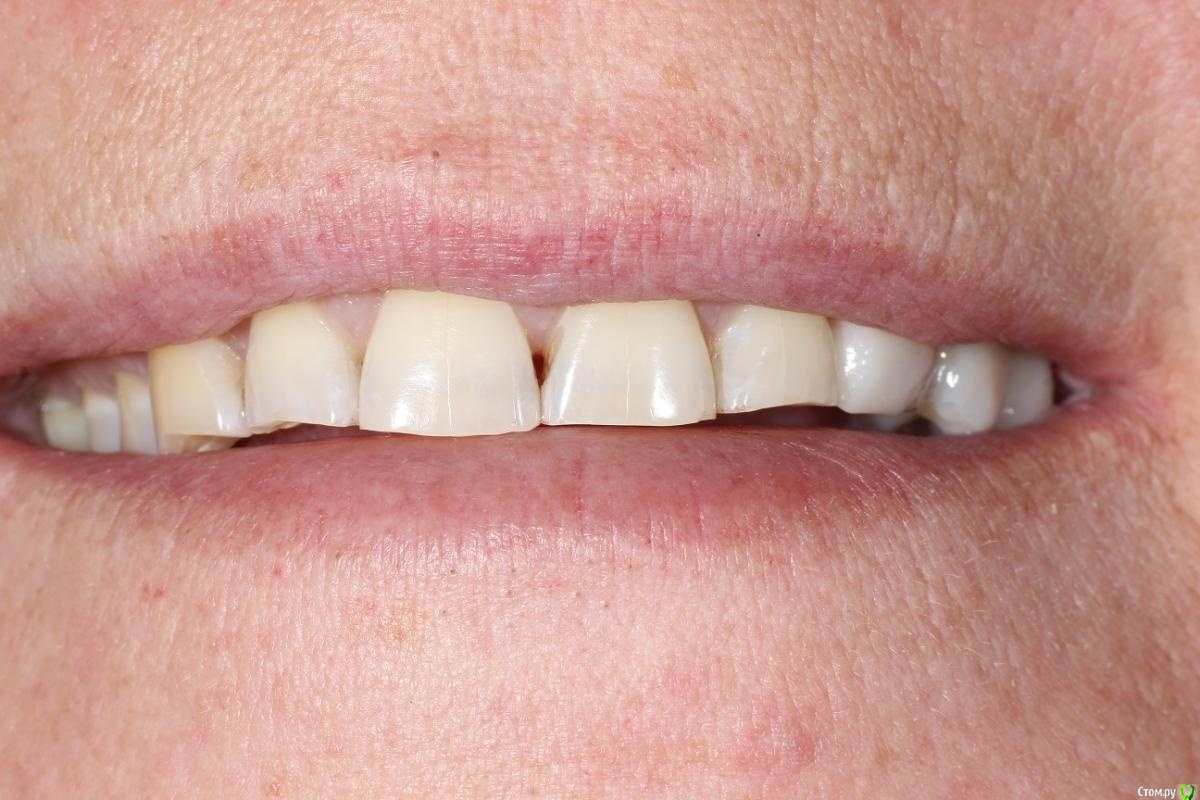

kuziy12 Опубликовано 2 ноября, 2020 Поделиться Опубликовано 2 ноября, 2020 Имплантация с синус лифтингом. Беда с позицией 2.3. Коронки на cad\cam, наносил розовую керамику и красил все сам. Сваливать не на кого) До: После имплантации: Формики: Десна: Постоянная конструкция: Улыбка: 3 Ссылка на комментарий

kuziy12 Опубликовано 9 октября, 2021 Автор Поделиться Опубликовано 9 октября, 2021 Дабы не плодить темы, выложу тут. Докрутил пациента полностью)) Ортопедия тоже моя. От переустановки импланта в области клыка отказалась. Ссылка на комментарий

Карен Аванесов Опубликовано 11 октября, 2021 Поделиться Опубликовано 11 октября, 2021 Ну вот, поздравляю Вас, получили благословение от Большого Зеленого, таперча работе служить 10 лет не меньше. 16 часов назад, Большой Зеленый сказал: Проблемы будут обязательно... а меня стертый клык насторожил, а работа жить будет, во рту чисто. 1 Ссылка на комментарий